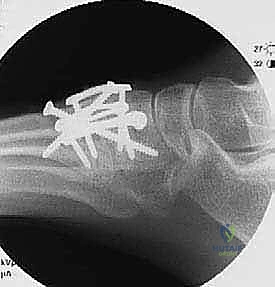

First TMT Joint Definitive Stabilization:

- "We'll start with the first TMT joint. Take a 3.5-mm drill sleeve and place it over the more dorsal 0.062 K-wire (the one from the medial cuneiform to the first metatarsal). Use cautery to mark the angulation of this wire on the bone. This helps us maintain the trajectory."

- "Carefully back out the 0.062 K-wire, ensuring the drill sleeve remains fixed in position. Now, using the 3.5-mm drill bit, drill through the near cortex of the medial cuneiform. Then, switch to a 2.5-mm drill bit to create the pilot hole in the far cortex of the first metatarsal. This differential drilling creates a lag effect."

- "Measure your screw length. Countersink the screw head to prevent prominence and soft tissue irritation. Now, insert a 3.5-mm cortical screw in a lag manner. Feel that compression as it bites into the far cortex. That's what we want."

- "Repeat these steps for the second screw, which goes from the first metatarsal to the medial cuneiform. Place a 3.5-mm drill sleeve over the K-wire, mark the trajectory, remove the K-wire, drill with 3.5mm through the near cortex (first metatarsal) and 2.5mm through the far cortex (medial cuneiform), measure, countersink, and insert the 3.5-mm cortical lag screw."

- "Confirm placement and compression with fluoroscopy."